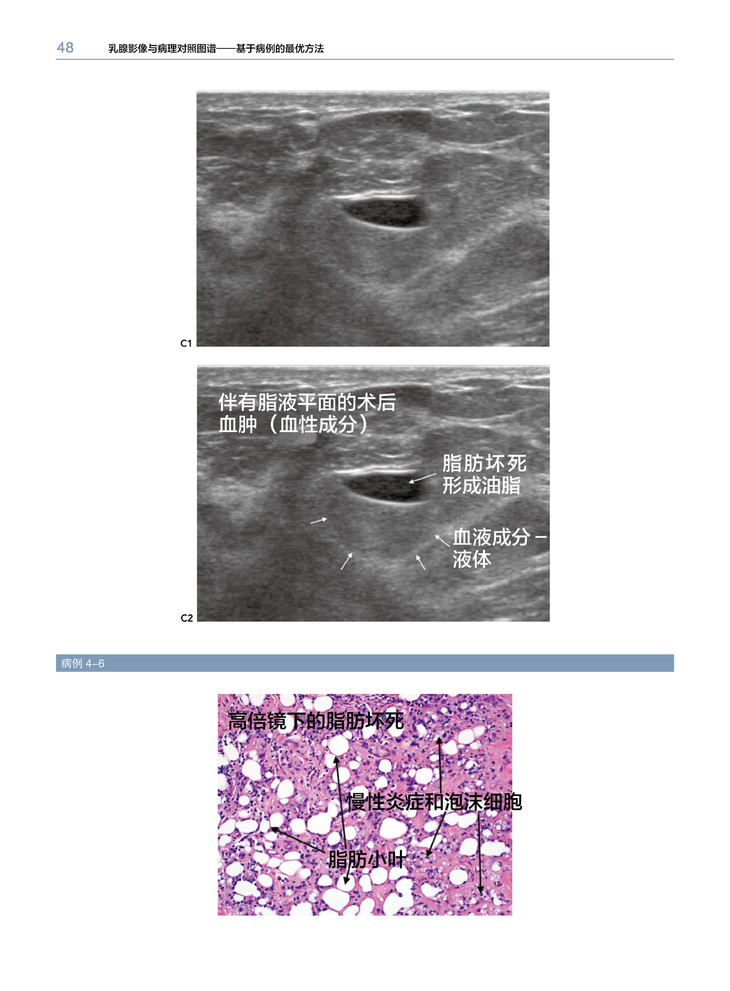

1.这本图集通过乳腺X线摄影或超声图像解释了乳腺影像 “怎样形成”和“为什么形成”的问题。应用病例优先选择的模式与你讲述了大量的常见和不常见的影像图像,与病理相结合阐述结果,帮助读者建立分析病例的能力,这样可以在诊断乳腺病例时信心十足。

2.对病例认识能力的提高,有赖于对病理描述分类的识别(例如肿块、钙化、结构扭曲等等及不太常见的恶性特征),而不是最后的病理诊断。

3.学习应用形状和边界去评估肿块,应用形态和分布去评估钙化,从重叠组织中辨别结构扭曲。领会如何应用大部分特征鉴别良性与恶性的可能性。

乳腺X线摄影和超声影像是乳腺影像检查最常用的两种方法。本书针对临床经常出现的有关乳腺癌影像表现,进行全面分析、归纳。乳腺癌主要是以三种形式表现的:肿块、钙化和结构变形。这本书主要分成以上3个主要部分,第四部分主要包括一些与恶性乳腺癌相关的重要影像表现。全书以病例为主,一共有400多个病例,文字简练,图片清晰,有病例的影像检查图,病理图,代表性强,能为各级影像科、乳腺科医生提供宝贵的参考价值。